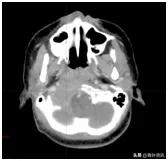

这可把珊珊爸爸妈妈急坏了,辗转多家大医院,颈部核磁共振检查发现颈椎、枕骨骨质广泛破坏、周边软组织形成(图一),后经病理检查确诊为朗格汉斯细胞增多症,是一种良性病!

图一 治疗前CT

但是随后医生的交待又让他们凉了半截,因骨质破坏范围较大,且位置特殊,无法手术治疗,如果病情进一步发展,随时可能出现颈椎骨折危及生命。